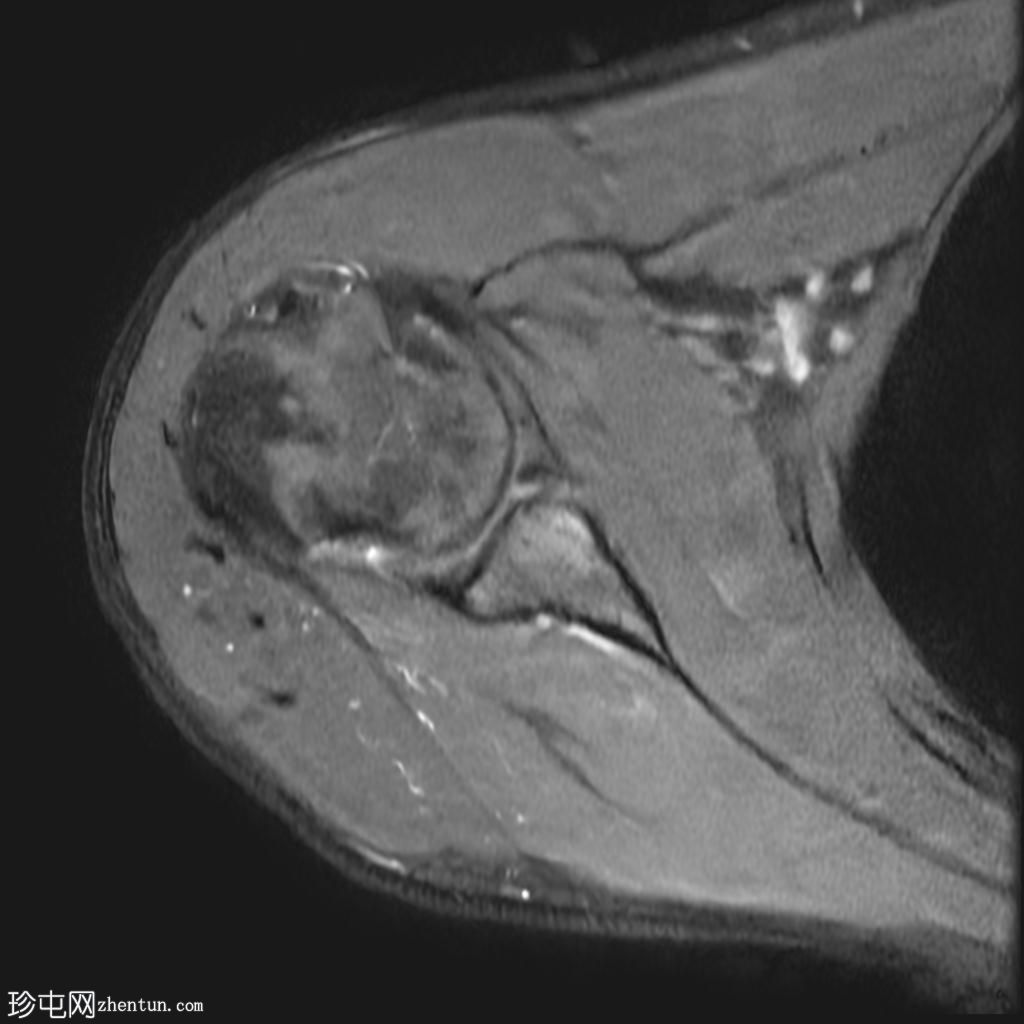

右肩外伤。

年龄:25岁

性别:男

MRI

轴位PD加权像

脂肪抑制像

Bankart损伤伴前盂唇及下方骨髓水肿

Hill-Sachs缺损表现为骨性压陷,肱骨头后外侧及下方骨髓水肿/挫伤

冈上肌腱关键区纤维肌腱病

MRI结果符合肩关节前脱位伴Hill-Sachs缺损和Bankart损伤的

影像

学表现。